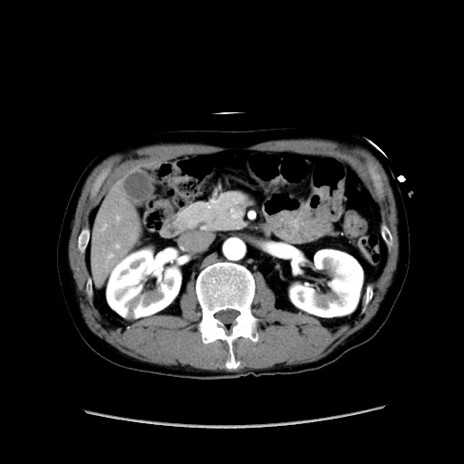

症例37(横断像)

【症例】40歳代 男性

【主訴】腹痛

【現病歴】4時間ほど前に電車に乗車中に臍部上より腹痛出現。徐々に増悪し起立困難となり、救急外来受診。生ものは数日食べていない。今朝お雑煮を食べた。

【身体所見】BT 36.8℃、BP 117/84mmHg、HR 91/min、SpO2 97%、苦悶様、腹部:臍上部広範囲圧痛あり、反跳痛±

【データ】WBC 8100、CRP 0.03